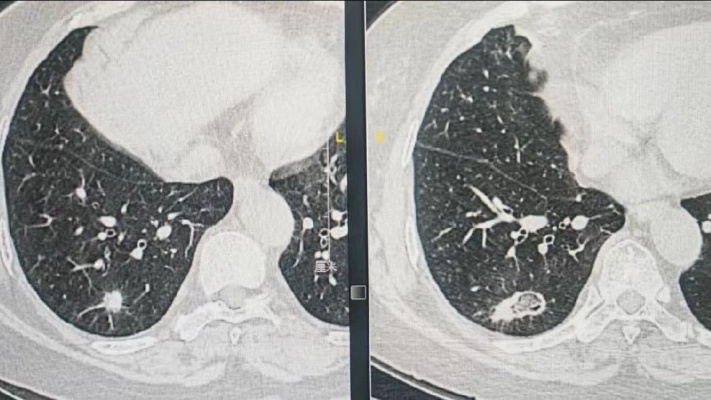

还有一名69岁女性患者,因右肺亚实性结节入院,恶性结节可能性大,医生建议观察3个月后复查或外科手术切除,也可以微创热消融治疗,微波消融可加热病灶及周边亚临床病灶达110℃—130℃使肿瘤组织凝固性坏死,以达到微创治疗肿瘤目的。

经过肿瘤科医生与家属的充分沟通,最终选择微创热消融治疗。10月11日,肿瘤科张利锋主任医师在CT导航下为患者进行右肺结节经皮微波消融术,手术顺利。术前后CT片对比可见该结节已被完全热覆盖,达到完全消融目的。